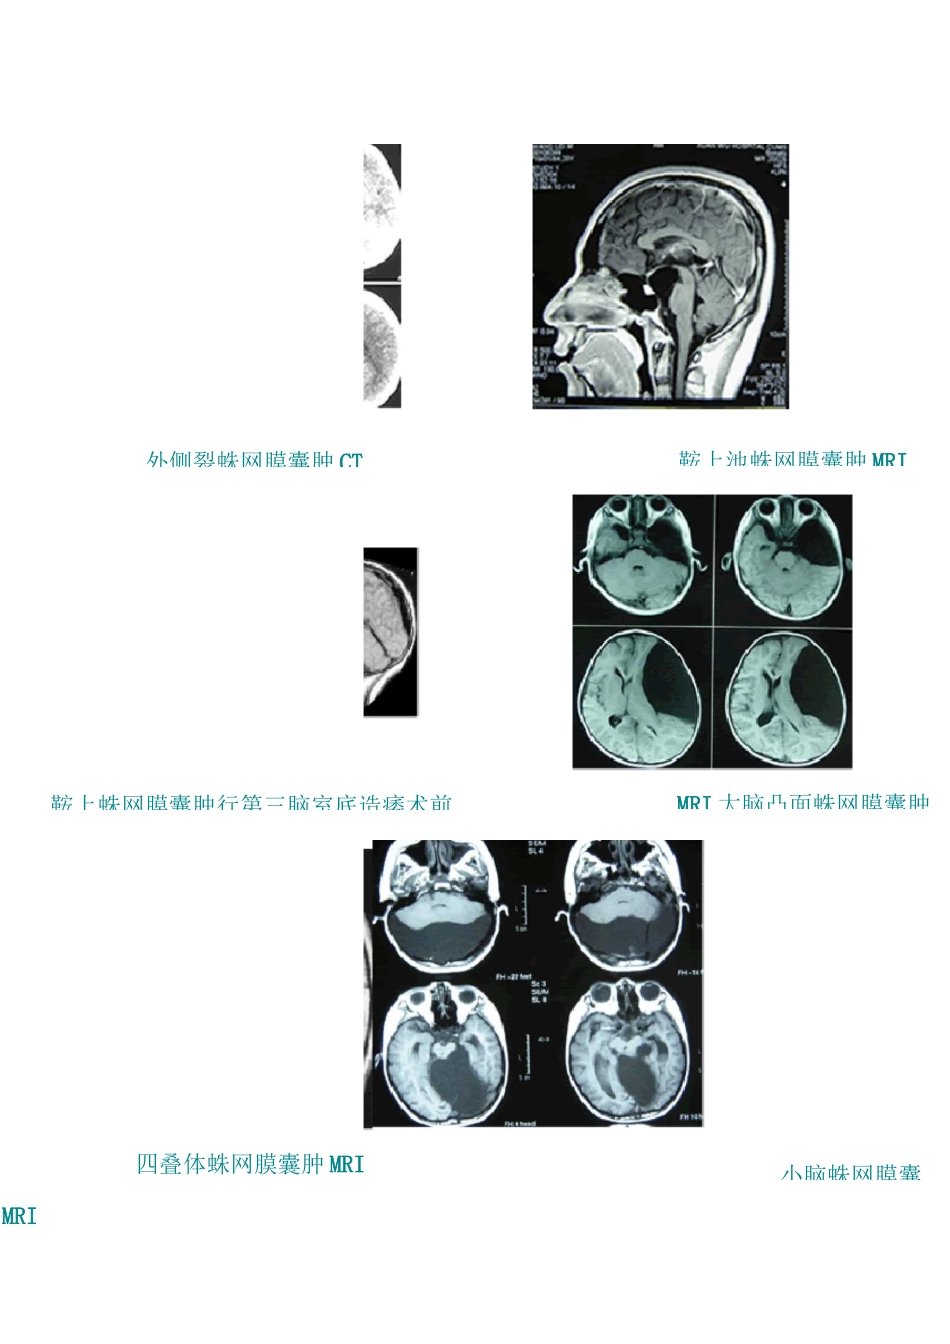

一、什么是蛛网膜囊肿蛛网膜囊肿(arachnoidcyst,AC)是脑或脊髓实质外囊性占位性病变,属非肿瘤性,由一透明的蛛网膜包裹,与脑室和蛛网膜下腔无交通,囊液呈无色或微黄色透明状。Howship1819 年和 Bright1931 年首先报道。二、蛛网膜囊肿的发病原因先天性蛛网膜囊肿发生的相关知识是相当有限的。根据大多数可靠的病因学描述,蛛网膜囊肿源于蛛网膜母细胞发育失常导致一个隔膜分裂或重迭。也有学者认为蛛网膜囊肿发源于蛛网膜与硬脑膜外层的原始间叶细胞发育缺陷形成蛛网膜腔隙进一步发展成蛛网膜囊肿,胚胎发育早期不正常的脑脊液流动异常也可能形成蛛网膜囊肿。继发性蛛网膜囊肿为出生后感染、外伤、出血等引起蛛网膜粘连,脑脊液被包裹形成的囊肿,内层隔膜存在炎性细胞和铁质。关于蛛网膜囊肿增大的原因存在争议,假说之一认为蛛网膜囊肿内液和脑脊液之间存在渗透压差,但这种解释同囊液与脑脊液性质相似的特征相矛盾。目前被广泛接受的蛛网膜囊肿逐步增大的原因有两个,第一、由于蛛网膜囊肿囊壁存在分泌功能,酶超细胞生物试验证明囊壁存在具有分泌功能的结构。Na-K 三磷酸腺酐酶、碱性磷酸酶可使脑脊液向囊内移动。第二、假设在解剖上存在囊内与蛛网膜下腔之间的单向活瓣,这种通路允许脑脊液向囊内移动。三、蛛网膜囊肿的分类:(一)根据组织学将蛛网膜囊肿分为两种类型:1、单纯蛛网膜囊肿。蛛网膜细胞层可能有分泌 CSF 功能。2、复杂型蛛网膜囊肿。囊壁更为复杂,含有神经胶质,室管膜和其他组织。(二)病理学上将蛛网膜囊肿分为:1、真性蛛网膜囊肿。蛛网膜两层间分离成封闭囊袋,其间充满脑脊液而构成的囊肿,与蛛网膜下腔不相通。2、假性蛛网膜囊肿。囊壁由蛛网膜和软脑膜组成,囊腔与蛛网膜下腔有一狭窄的通道,脑脊液可以互相流动。这一分法可以帮助对脑组织影响的认识,亦可确定是否需要外科处理。(三)根据发病原因将蛛网膜囊肿可分为:1、先天性蛛网膜囊肿2、继发性蛛网膜囊肿(四)根据病变部位将蛛网膜囊肿分为:1、颅内蛛网膜囊肿(1)幕上蛛网膜囊肿a)外侧裂囊肿 b)鞍区囊肿 c)大脑凸面蛛网膜囊肿b)裂囊肿c)四叠体囊肿(2)、幕下蛛网膜囊肿a)小脑囊肿b)桥小脑角囊肿c)四脑室囊肿2、椎管内蛛网膜囊肿(1)硬膜下囊肿(2)硬膜外囊肿3、颅骨板障内蛛网膜囊肿同部位蛛网膜囊肿影像表现:外侧裂蛛网膜囊肿 CT鞍上池蛛网膜囊肿 MRI鞍上蛛网膜囊肿行第三脑室底造痿术前MRI 大脑凸面蛛网膜囊肿小脑蛛网膜囊四...